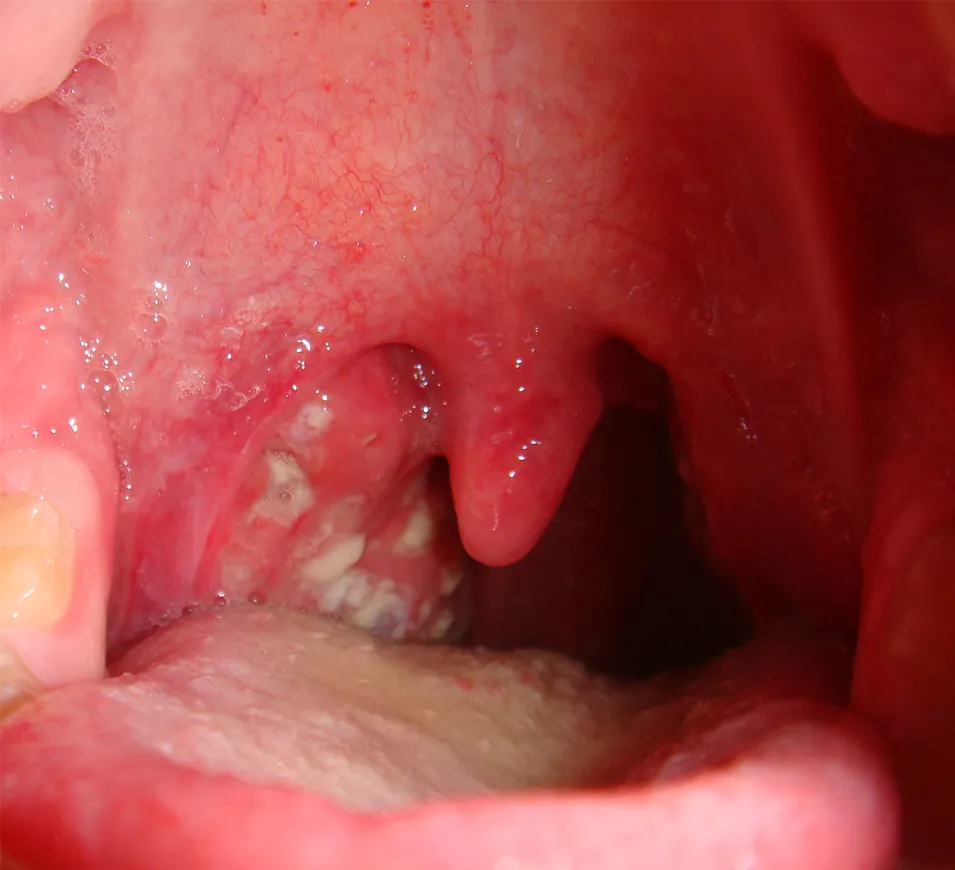

Kiedy migdałki zaczynają boleć, pierwsza myśl często dotyczy anginy. Jednak ból migdałków może mieć różne podłoże, a rozróżnienie infekcji wirusowej od bakteryjnej jest kluczowe dla właściwego leczenia. Infekcje wirusowe są znacznie częstsze i często towarzyszą im inne objawy przeziębienia, takie jak katar, kaszel, chrypka, ból mięśni czy ogólne osłabienie. Gorączka zazwyczaj nie jest bardzo wysoka. W takich przypadkach antybiotyki są nieskuteczne. Z kolei infekcje bakteryjne, najczęściej angina paciorkowcowa, charakteryzują się nagłym początkiem, bardzo silnym bólem gardła, wysoką gorączką (często powyżej 38,5°C), trudnościami w połykaniu oraz charakterystycznymi białymi lub żółtymi nalotami na migdałkach. Katar i kaszel są zazwyczaj nieobecne.

Jednym z najbardziej alarmujących objawów jest pojawienie się białych lub żółtych nalotów na migdałkach, często połączonych z bardzo silnym bólem gardła i wysoką gorączką. To klasyczne objawy anginy ropnej, która najczęściej jest wywoływana przez bakterie (paciorkowce). W takim przypadku leczenie antybiotykiem jest zazwyczaj konieczne. Nieleczona angina bakteryjna może prowadzić do poważnych powikłań, takich jak gorączka reumatyczna czy kłębuszkowe zapalenie nerek. Dlatego, widząc takie naloty, nie zwlekaj z wizytą u lekarza.Jakie antybiotyki są najczęściej przepisywane na bakteryjne zapalenie migdałków?

- Obecność białych lub żółtych nalotów na migdałkach. Jest to silne podejrzenie anginy ropnej, która wymaga leczenia antybiotykiem.